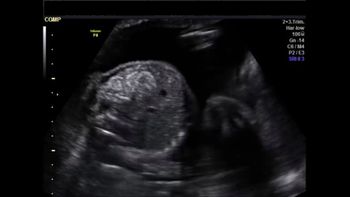

QUIZ: These images show something isn't quite right in a woman who is 34 weeks pregnant.